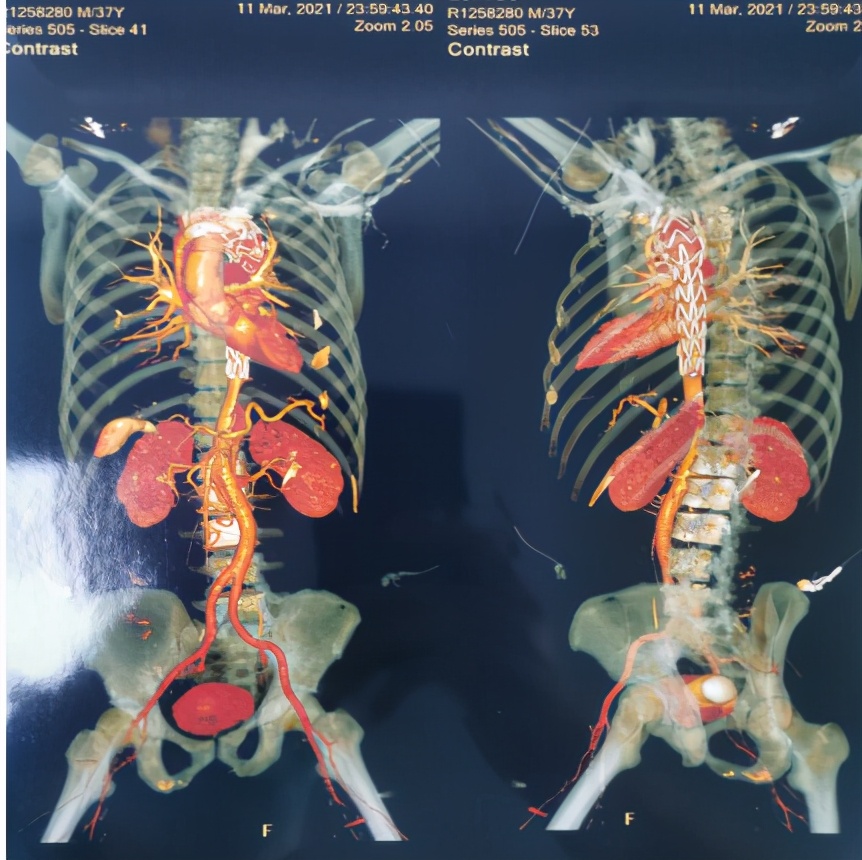

3月11日,患者血压、脉搏、心率等各项生命监测指标控制良好,病情趋于稳定。罗湖医院血管外科主任黄智勇主任带领团队为患者行胸主动脉造影+胸主动脉腔内隔绝术。术中见主动脉夹层(stanford B型),定位释放支架,精准定位、精确制导,效果立竿见影,无缝连接,假腔完全消失,无内漏,血流通畅(见图3)。

图3

这是一项微创手术,患者仅在右侧腹股沟区及左上肢肘部动脉皮肤区2处各有一不超过0.5cm的切口。手术过程顺利,术后生命体征平稳,术后四肢皮肤温暖,远端动脉搏动良好。